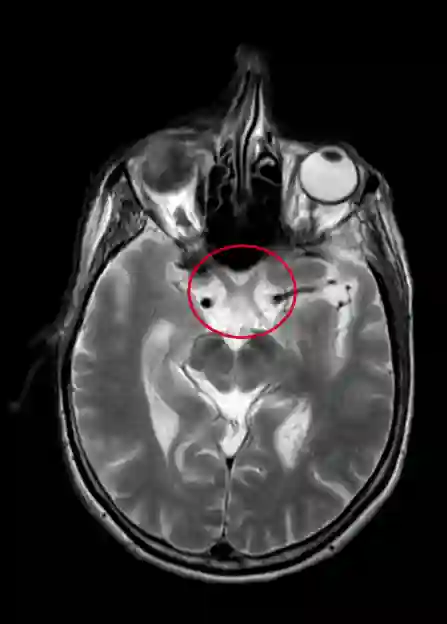

Chiasma opticum im MRT

Darstellung des Chiasma opticum (innerhalb der roten Markierung) in einer axialen T2 MRT Sequenz des Schädels.